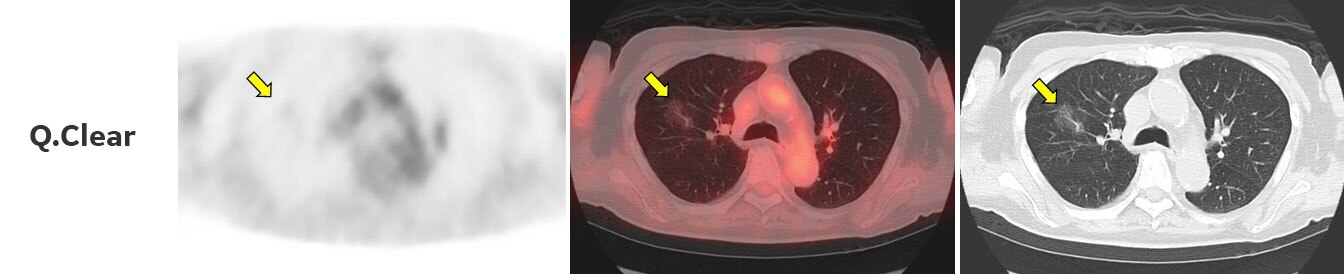

CT上にて肺野にすりガラス像を認め、PET画像上で淡いながらも集積を認められます(Fig.2)。

3D-OSEM(従来法)で再構成した画像では、すりガラス像に一致した部位の集積は明らかではありません。Q.Clearを用いて再構成した画像では、淡いながらもすりガラス像に一致した集積が認められます。また、Q.Clearを用いて再構成した画像では、従来法と比べてノイズが低減されています。

すりガラス像部でのSUV測定結果は、従来法でSUVmax 0.69、SUVmean 0.48、Q.ClearでSUVmax 0.81、SUVmean 0.59となっており、Q.Clearで集積は増加しています。

また、すりガラス像の周辺肺野では従来法でSUVmax 0.58、SUVmean 0.43、Q.ClearでSUVmax 0.46、SUVmean 0.39となっており、Q.Clearで集積は低下し、そのピクセル毎のばらつきも抑えられています。

従来法では病変部とその周囲においてSUV値の変化量が少なく、集積無しとなっていたものが、Q.Clearでは淡いながらもコントラストが得られて集積として認めるようになりました。